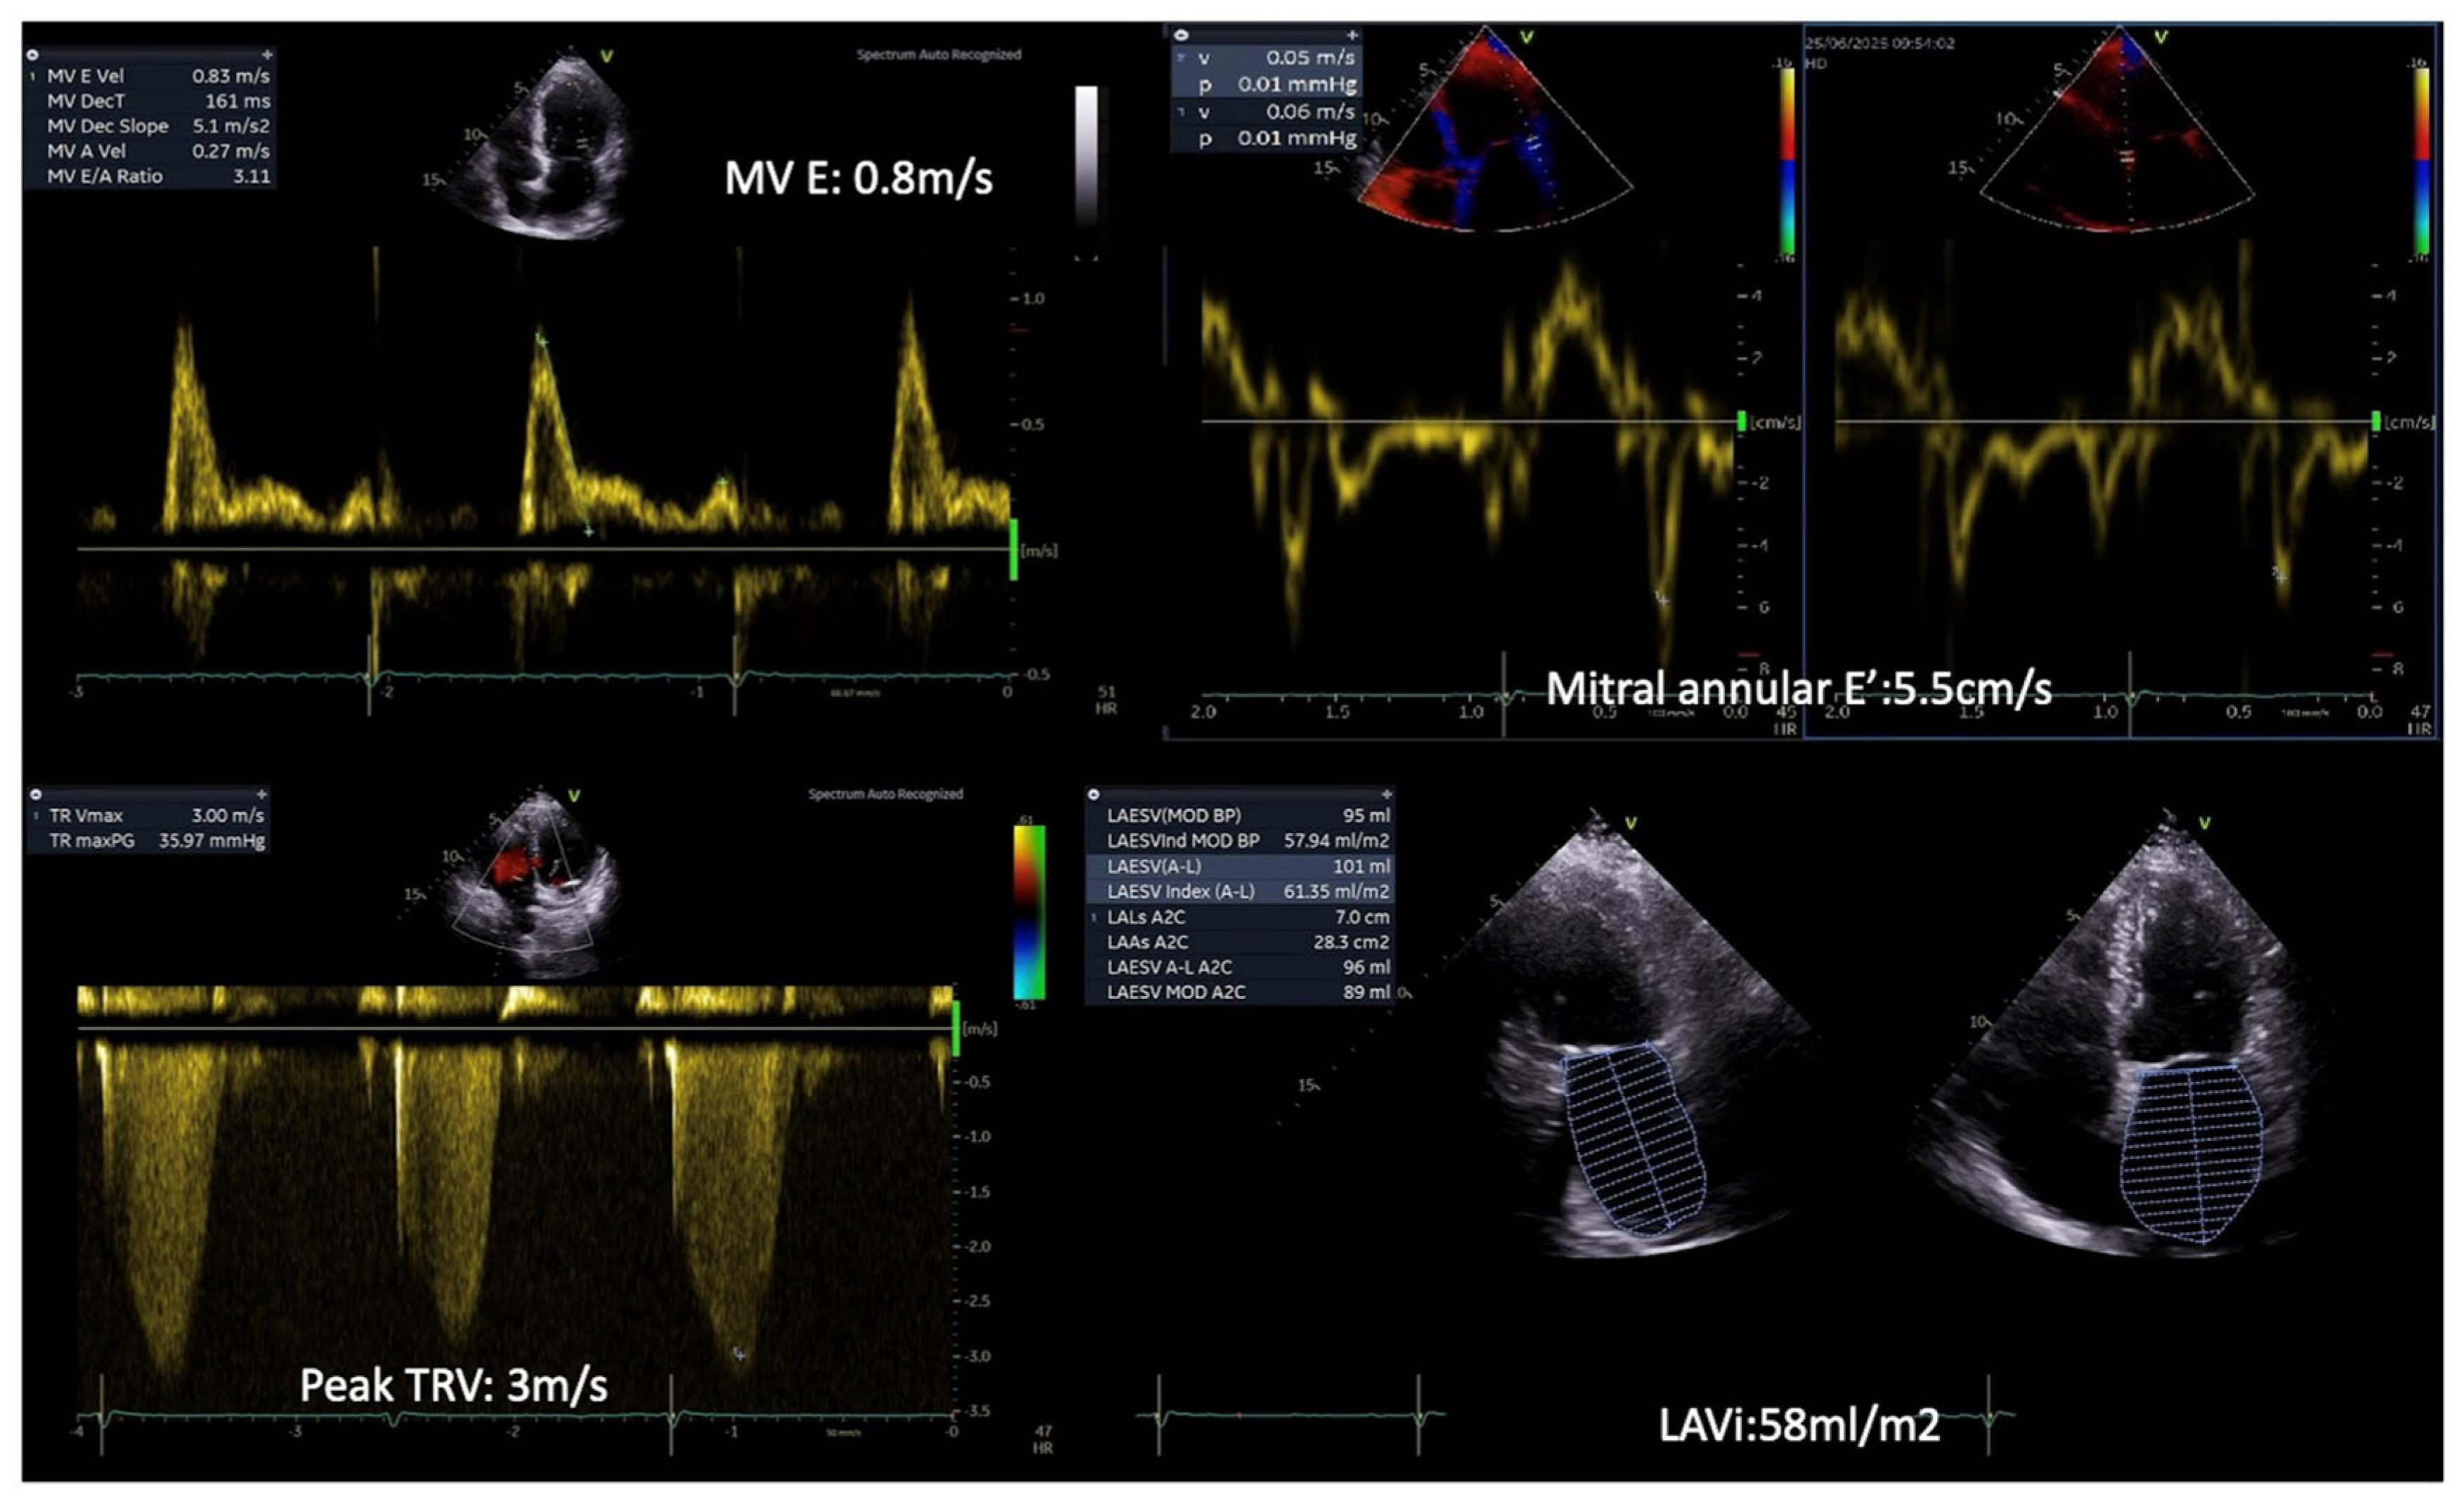

| Diastolic dysfunction | E/A, E/e’, e’ using TDI, LAVi, TRVpeak using Doppler | Influenced by age and preload; requires integration of multiple parameters | -Septal E/e’ ratio >15 in diabetic patients is associated with future HF and increased mortality. |

3.2. Diastolic Dysfunction